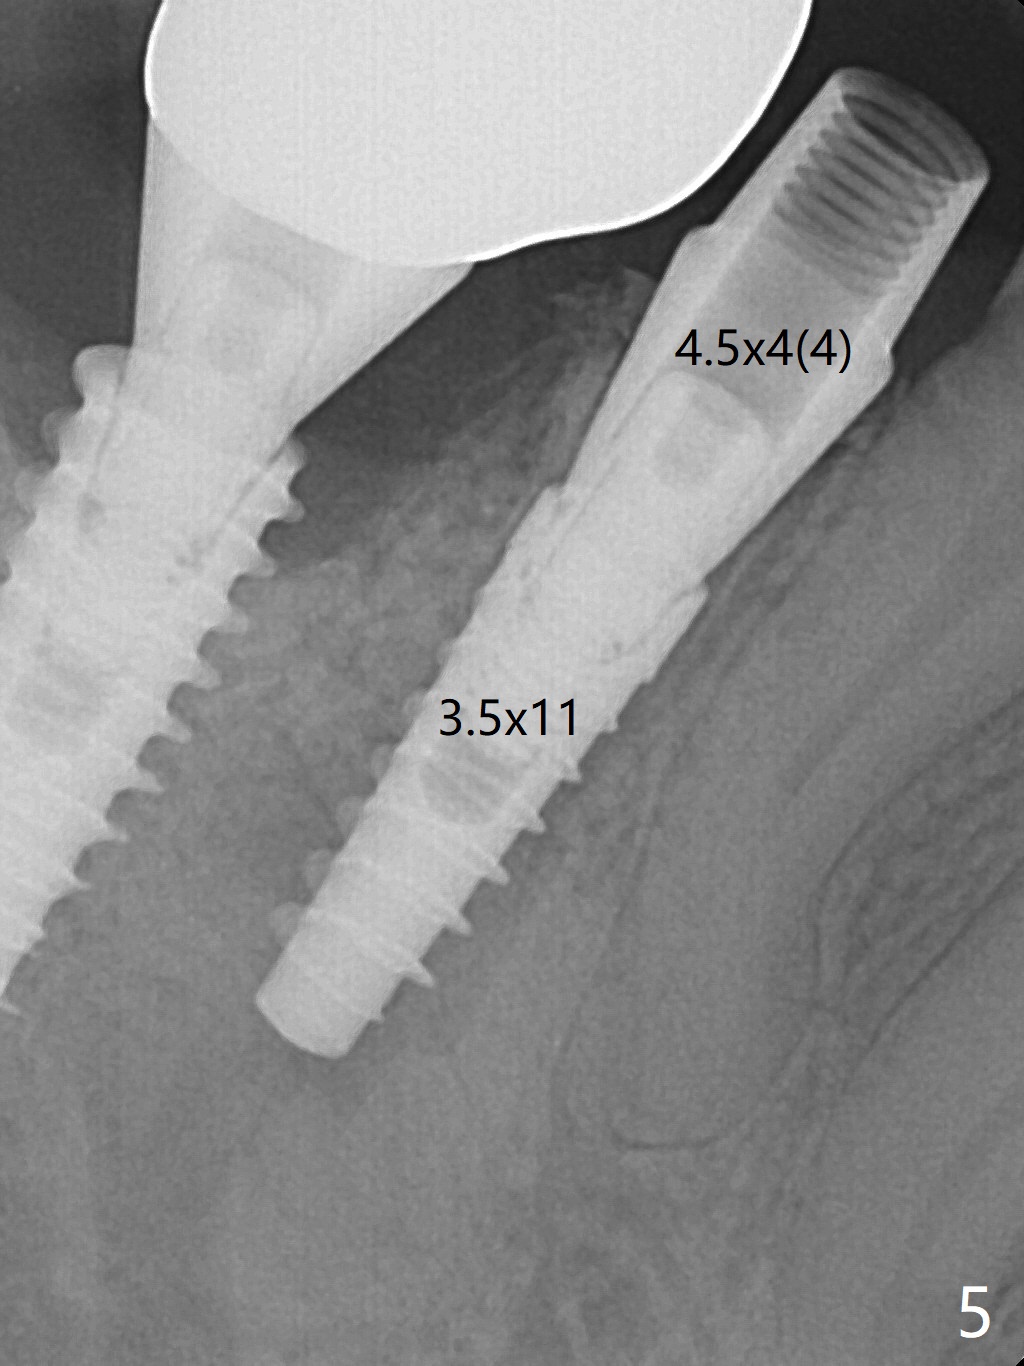

The tooth #29 has mild persistent pain radiating to the temple with mild percussion and mobility I 4.5 months post apicoectomy; the buccal recession is noticeable (Fig.1). Granulation tissue and bone graft are attached to the resected apex of the extracted tooth (Fig.2 <). The initial osteotomy with 1.5 mm drill is distal (Fig.3). After position adjustment with difficulty because of hard bone, osteotomy is finished with 2.8 and 3.2 mm Magic Drills (Fig.4). Following final drill, a 3.5x11 mm IBS implant is placed with insertion torque of 45 Ncm. With placement of a 4.5x4(4) mm abutment, Vanilla graft is placed in the buccal gap (Fig.5). Immediately postop CT shows that the implant is buccally placed (Fig.6,7 B). In fact after extraction (Fig.8), the initial osteotomy should start obliquely and as coronal and lingual as possible (Fig.9 red line). Following the initial penetration, the osteotomy should be straightened (Fig.10) so that the implant could be placed lingually (Fig11 green) to reduce buccal thread exposure. In fact there is also buccal thread exposure at #30 (Fig.12). The bone loss at #29 and 30 is minimal 4 months postop (#29, Fig.13 *)) and severe with periimplantitis at #29 one year post cementation (Fig.14). Incision will be made to exposure buccal threads of #29 and 30. If threads are within bone boundary, bone graft will be done with sticky bone after Titanium brush. If not, remove implant threads and bone graft. The worst scenario will be handled with implant removal (trephine bur 4/5 mm), either with bone graft or implant being placed lingually (IBS 3x11 mm 2-piece, to be buried, if needed (Fig.15)). Take preop photos to show #29 and 30 buccal recession and gingival erythema.